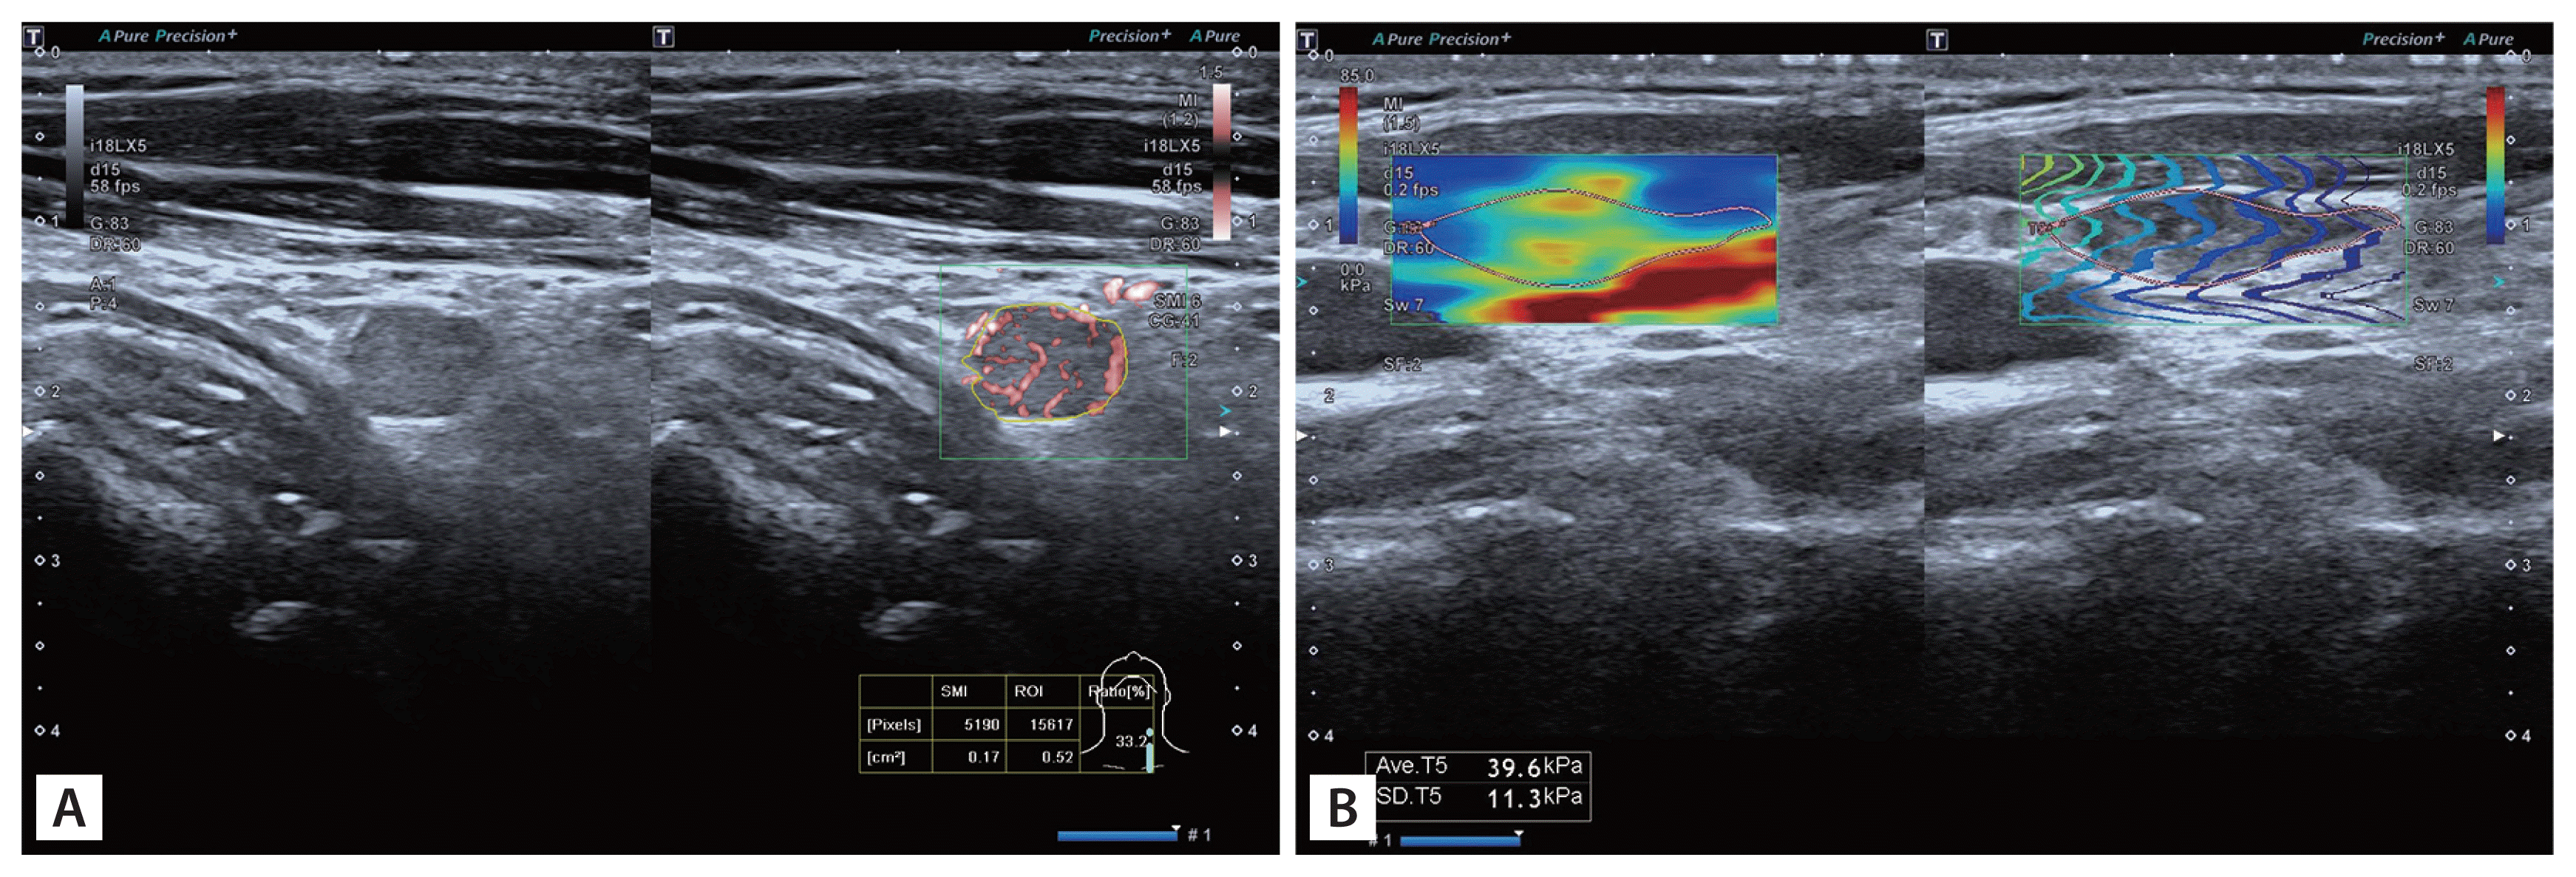

According to 2021 Korean Thyroid Imaging Reporting and Data System [17], we selected suspicious lymph nodes. Lymph nodes with any of the following features are defined as suspicious: cystic areas, hyperechoic foci (calcifications), cortical hyperechogenicity (focal/diffuse), or abnormal vascularization (peripheral/diffuse). We carefully evaluated the ultrasound features of the lymph nodes, including the presence or absence of a lymphatic hilum, the presence or absence of cortical hyperechogenicity, the presence or absence of calcification, the presence or absence of cystic components (Fig. 2) and the vascular pattern. There are four acknowledged vascular patterns, including hilar, peripheral, mixed and avascular or spot vascularity (Fig. 3). Mixed or peripheral vascularity was considered a malignant feature.

Four kinds of vascular pattern by SMI. (A) Hilar vascular. (B) Peripheral vascular. (C) Mixed vascular. (D) Spot vascular. SMI, superb microvascular imaging.